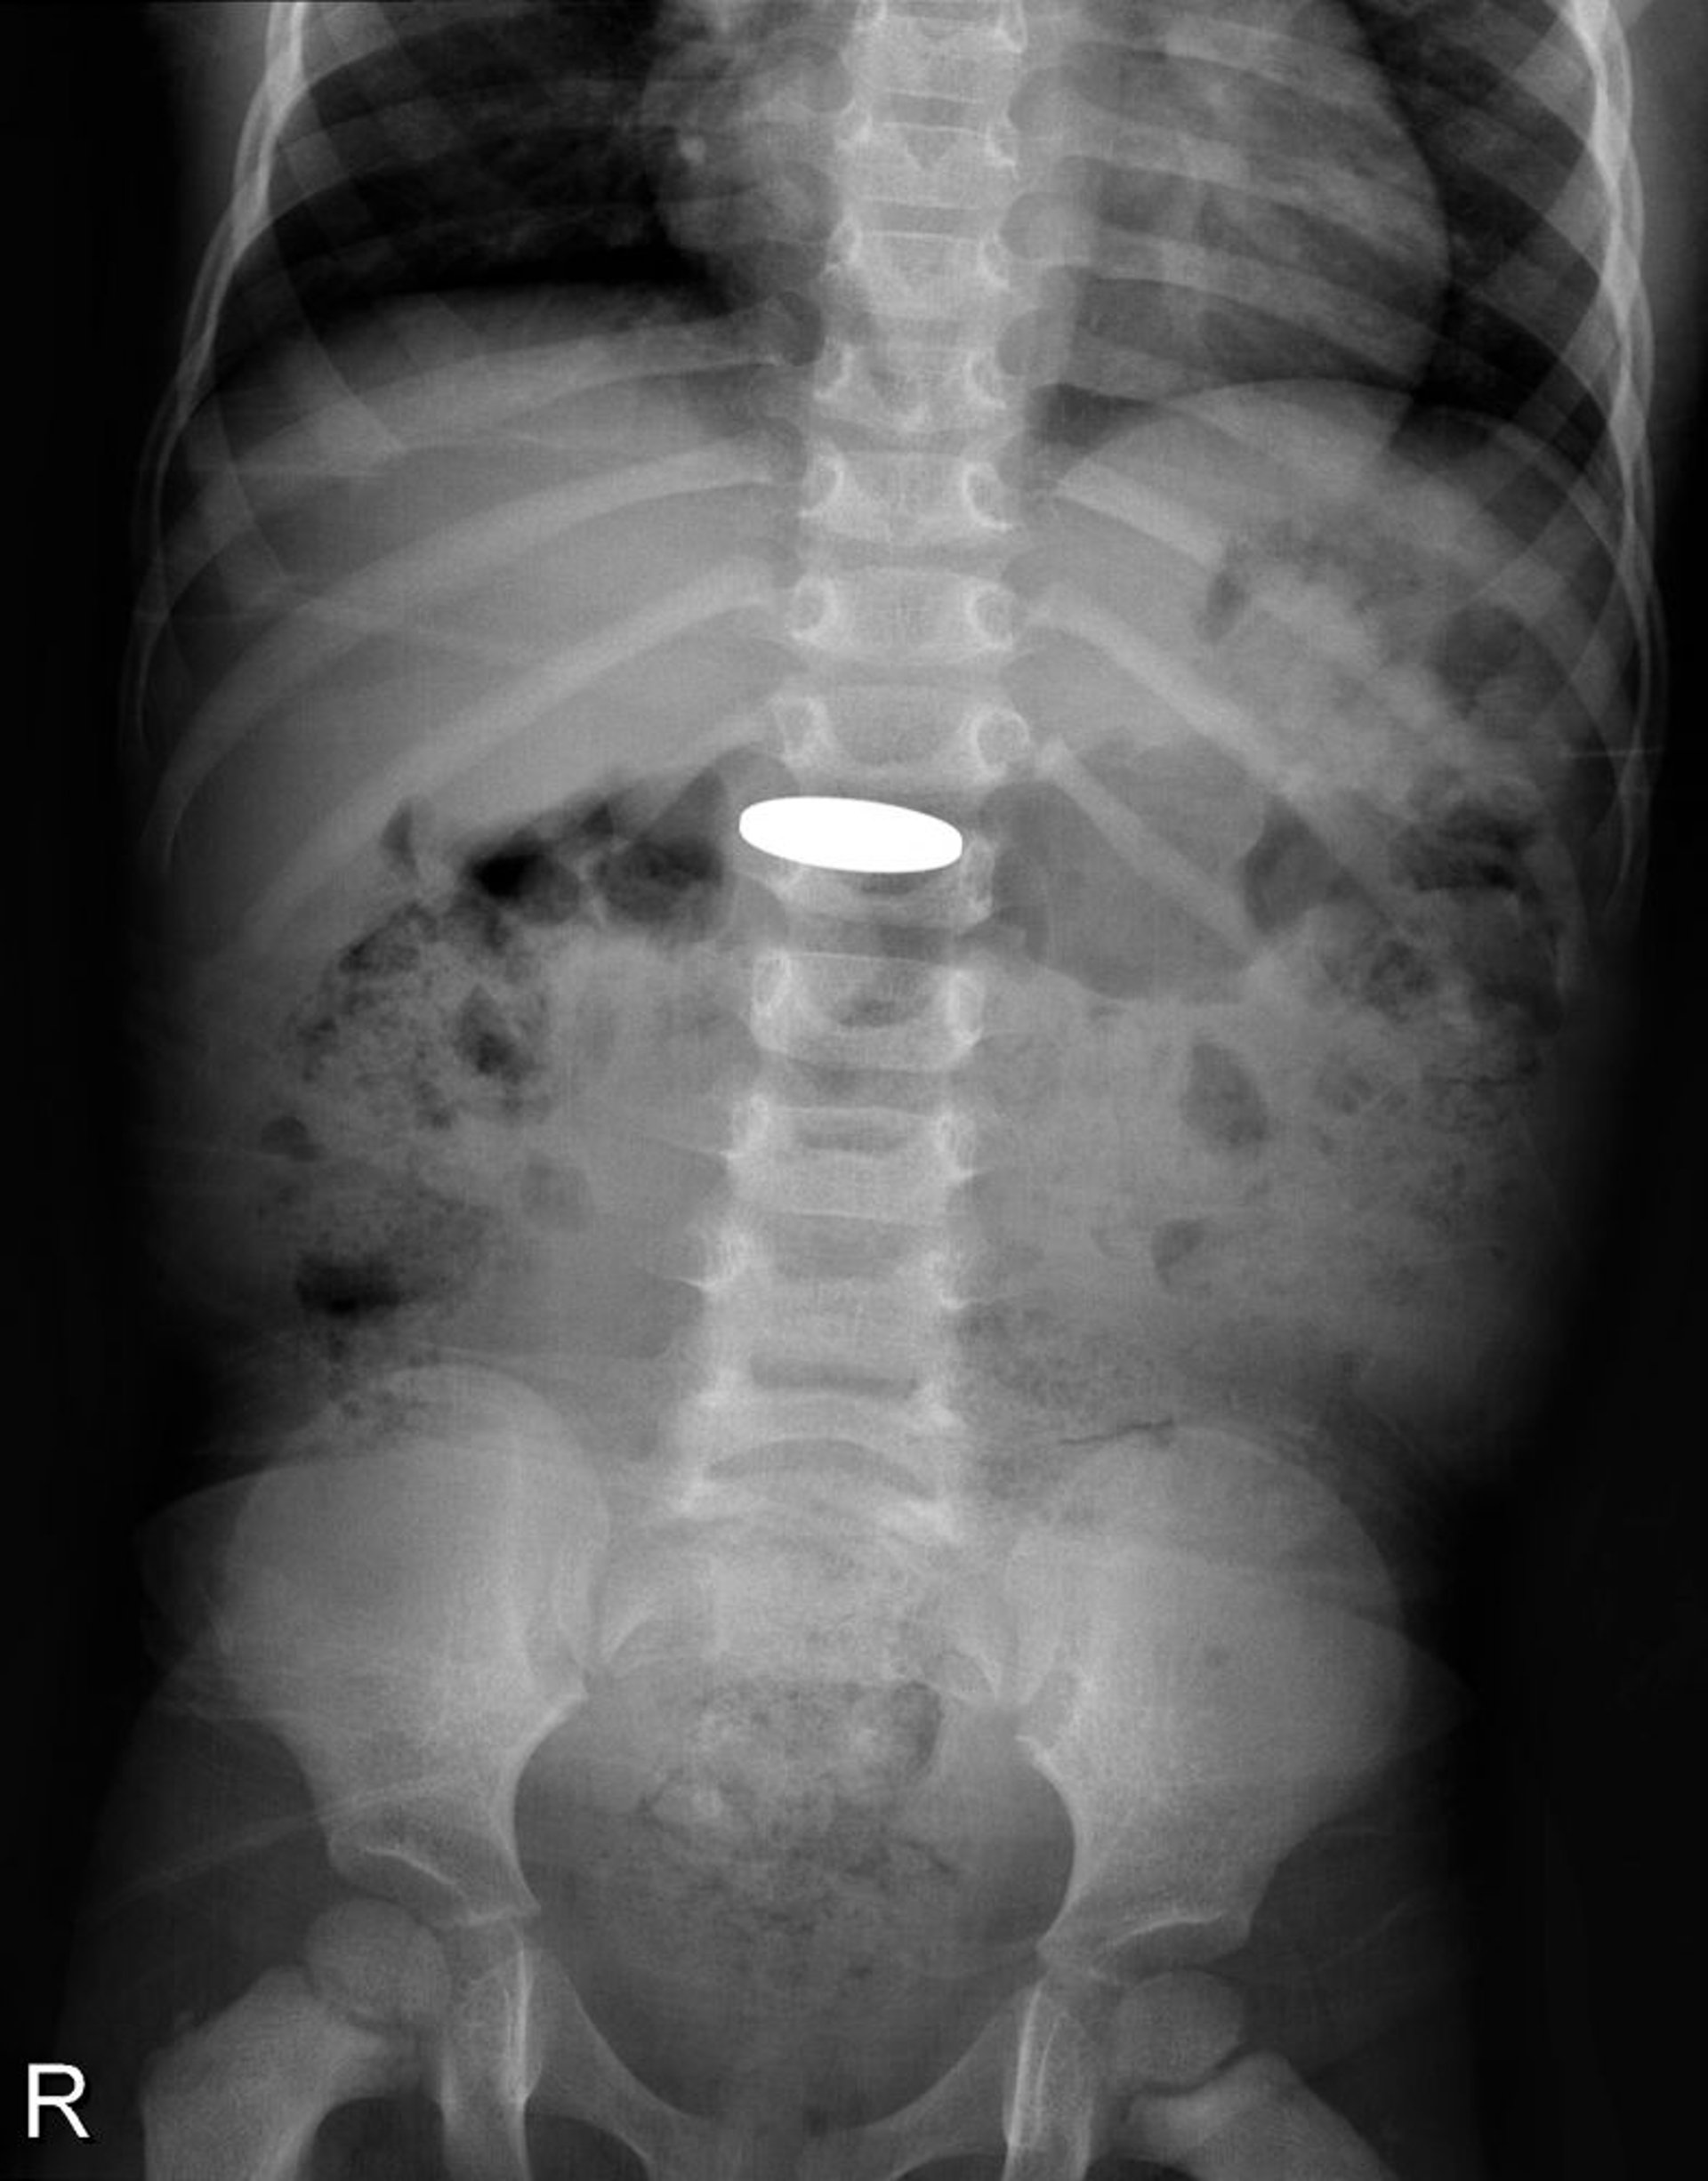

Corpo estraneo nel tratto digerente (radiografia)

La radiografia mostra una moneta ingoiata da un bambino piccolo.